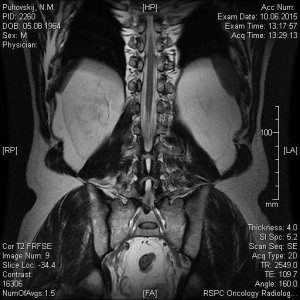

Сегодня сделали МРТ поясничного отдела позвоночника моему отцу. Результат записан на СD диск с множеством фото, заключение, соответственно, прилагается. Но для полной уверенности хотелось бы подтверждения иного специалиста. Основные симптомы: острые и постоянные боли в пояснице, периодически "отказывают" ноги (приходится постоянно менять свое положение-присесть, выгнуться, нагнуться, пройтись и т.п). Не маловажный факт, что около 5 лет назад с идентичными симптомами у папы обнаружили грыжу и удалили ее. Опыт имеется, а страх все равно присудствует. Помогите пожалуйста.

12.jpg48,8 КБ · Просмотры: 638

12.jpg48,8 КБ · Просмотры: 638 -